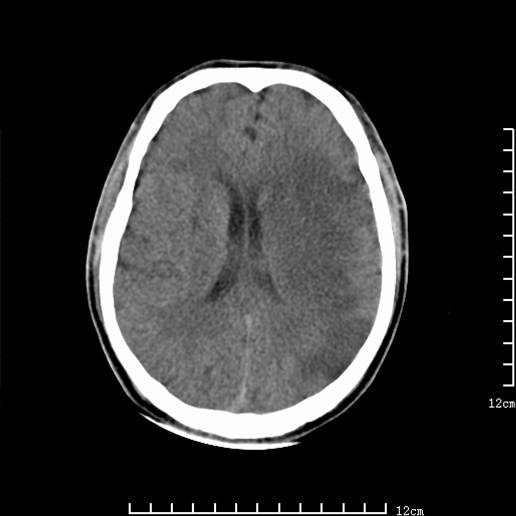

以下图像分别是3月25日凌晨及下午图像、3月27日、4月16日的ct图像。

4月16日

4月16日ct复查:符合出血性脑梗塞表现。

资料齐全,符合脑梗塞溶栓治疗后,血管再通而致的出血性脑梗塞。

支持出血性脑梗塞,可能因血管再通后,再灌注损伤所致。

4月16日ct复查:符合出血性脑梗塞表现